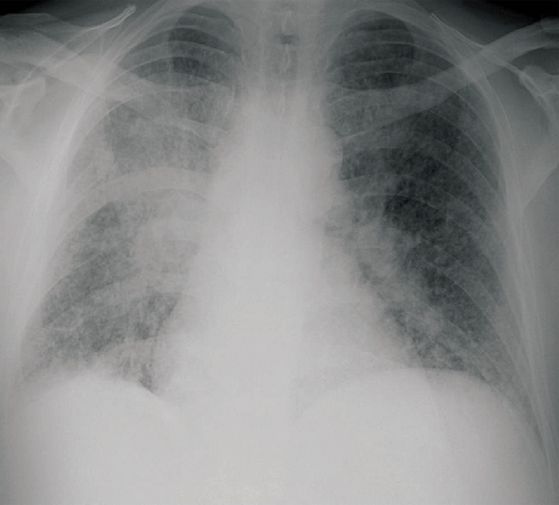

![Blastomycosis Americana (click on photo to enlarge) [source: CDC - Public Domain Image] Blastomycosis Americana](../../../images/north-american-blastomycosis-1z.jpg) |

Blastomycosis Americana |

Foto: CDC Atlanta (Public Domain Image).

X-thorax: Pralay K.

Sarkar (Wikimedia, Creative Commons License

3.0)